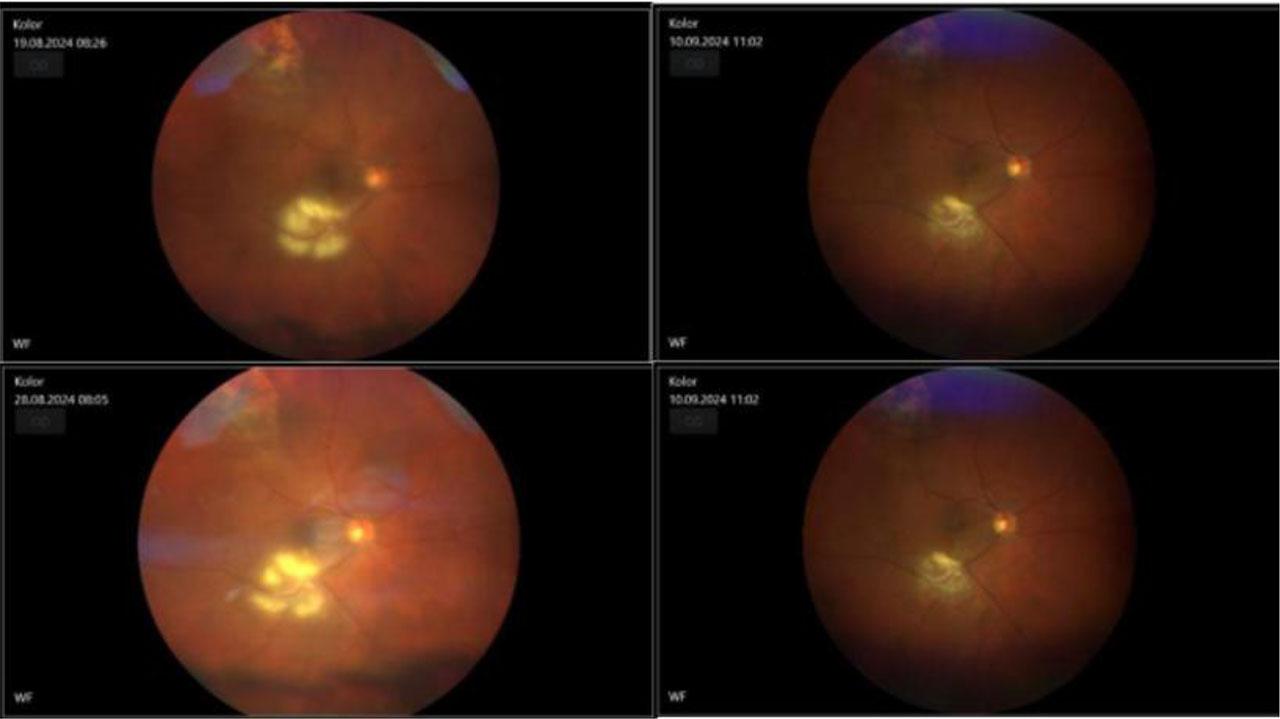

Fundus photo of the right eye with inflamatory chorioretinal changes –the left side pre-treatment and on the right site there’s an image made after the treatment

Fundus photo of the left eye with inflamatory chorioretinal changes – on the left side pre-treatment and on the right side there’s an image made after the treatment

Upon physical examination at the time of admission, the best-corrected visual acuity (BCVA) was as follows: right eye (RE): 0.25 sc, with a Snellen chart measurement of RE: 0.75 csph +1.0, and left eye (LE): 0.9 sc, with a Snellen chart measurement of LE: 0.5 csph +1.0. Intraocular pressure was measured at 14 mmHg in both eyes. The anterior segment was within normal limits. Examination of the fundus of the right eye revealed obscured details due to a hazy view, with floaters in the vitreous body. There was an inflammatory choroidal-retinal lesion in the inferior temporal vessel measuring 4 dd × 6 dd, accompanied by inflammatory condensation in the vitreous body (reflections obscured). Superiorly, there was a bright, elevated lesion with a small amount of pigmentation (2.5 dd × 2 dd) consistent with post-inflammatory scarring, without retinal detachment [Fig. 1]. In the left eye, floaters were noted in the vitreous body, with an inflammatory choroidal-retinal lesion in the area corresponding to the superior nasal vessel, exhibiting a longitudinal oval shape (5 dd × 3 dd) [Fig. 2].

In the following days of hospitalization, inflammation was reduced in the anterior chamber and vitreous body, and there was a decrease in choroidal-retinal inflammatory lesions. A decision was made to discharge the patient from the ophthalmology department with a continuation of systemic and topical treatment. Consultations in the infectious diseases and hematology outpatient clinics were recommended.

One week later, further inflammation reduction was observed during a follow-up examination. One month after the initiation of treatment, an increase in liver function tests was noted, leading to a change in the treatment regimen: pyrimethamine and folic acid were discontinued, and fluconazole was replaced with nystatin. Following the normalization of liver function tests, pyrimethamine was reintroduced. After one month, the objective examination revealed continued inflammation reduction, post-inflammatory scarring formation, and visual acuity improvement (BCVA in the right eye: 0.4 csph −2.0D; left eye: 0.9 sc) [Fig. 4]. The patient was regularly monitored every two weeks, with the intervals between follow-ups extended in subsequent months. Visual acuity in the right eye improved to 0.6 csph −0.75 and near vision to 0.5 csph +2.00. An OCT of the macula was performed, revealing RPE thinning and ERM with traction, while the foveal morphology in the left eye remained preserved [Fig. 5].